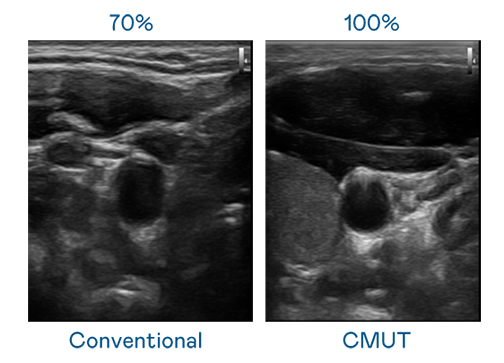

CMUT 技术是一种用电容式微机电元件来产生超音波讯号的技术。与传统 PZT 压电式技术相比,CMUT 频宽增加 30%,更宽频的超音波讯号让影像解析度大幅提升,是实现高影像品质医疗超音波扫描、促进精准医疗发展的关键技术。

超音波影像的解析度高低,首先取决于探头能发出的讯号频宽。五月天精品传奇网站免费观看完整 CMUT 可提供高清晰的超音波讯号,提供高频宽、高灵敏度、影像纹理细节更高的超音波影像,协助医护人员缩短影像判读时间及利用精准的医疗影像进行诊断。